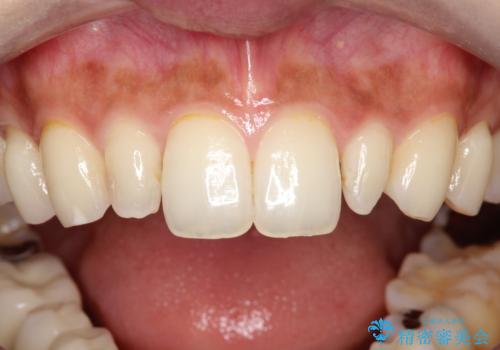

【オールセラミッククラウン】矮小歯の治療

- 矯正治療で配列した矮小歯をオールセラミッククラウンで修復治療を行いました。

すごく自然な仕上がりになり満足していただきました。

オールセラミッククラウンは、隣の歯に合わせて色調を調整することができるため非常に綺麗に仕上がります。